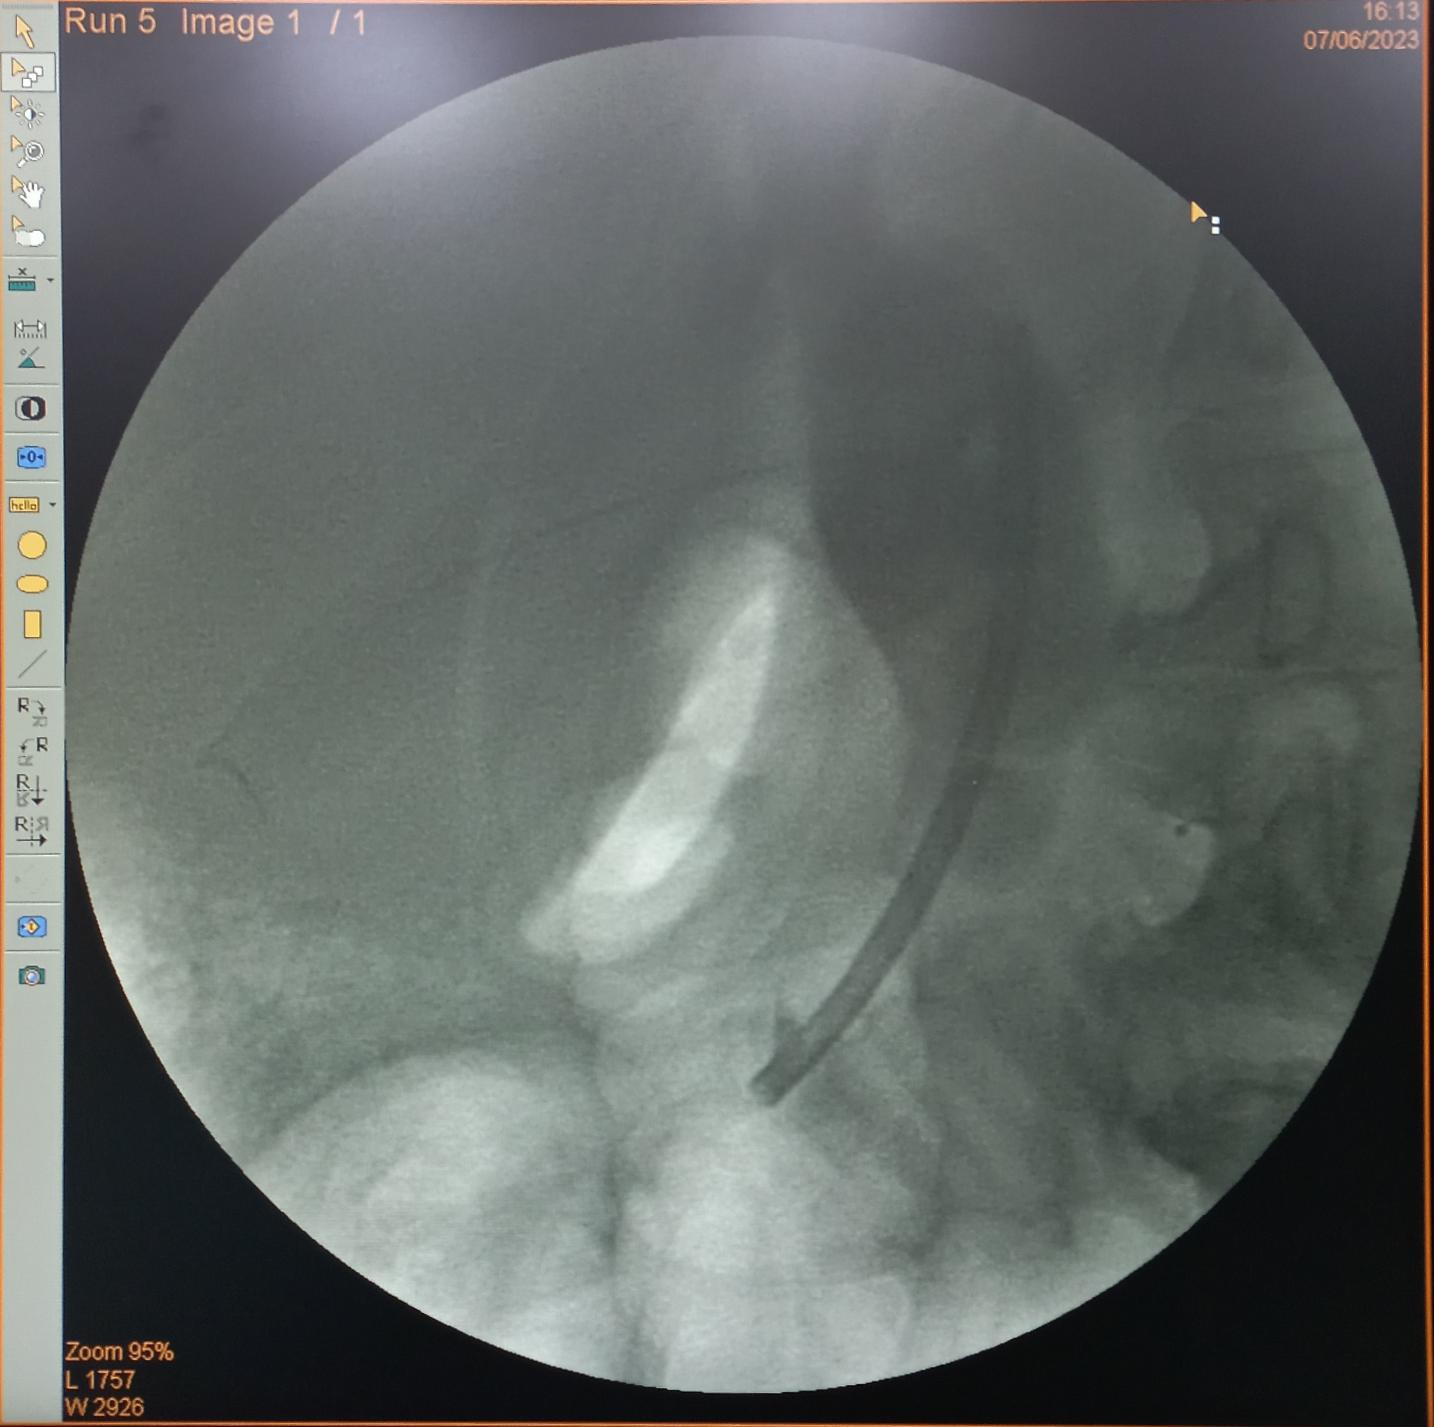

Đặt lại stent mới để dẫn lưu mật.

Trong quá trình can thiệp ERCP, nhận thấy đường mật có stent cũ đã tắc và bám sỏi, dịch mật không thoát ra được do hẹp đoạn cuối ống mật chủ, ekip can thiệp đã rút bỏ stent cũ và tiến hành đặt lại 1 stent khác để dẫn lưu ổ nhiễm trùng tạm thời.